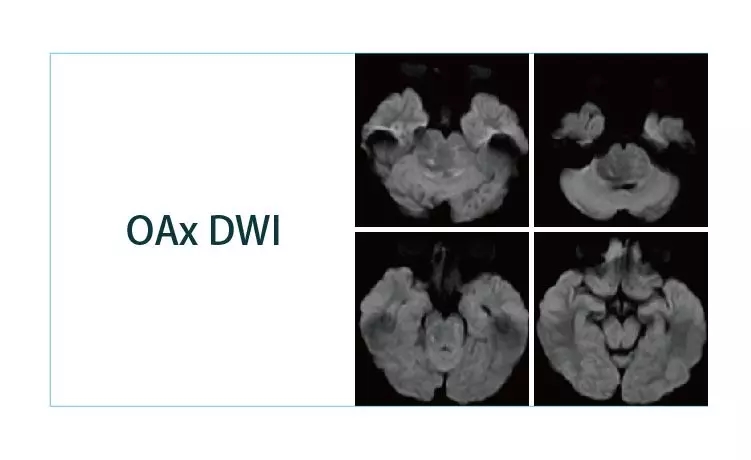

【朗润影像档案】磁共振影像病例分享(编号20190329)

2019-04-01 09:13:05